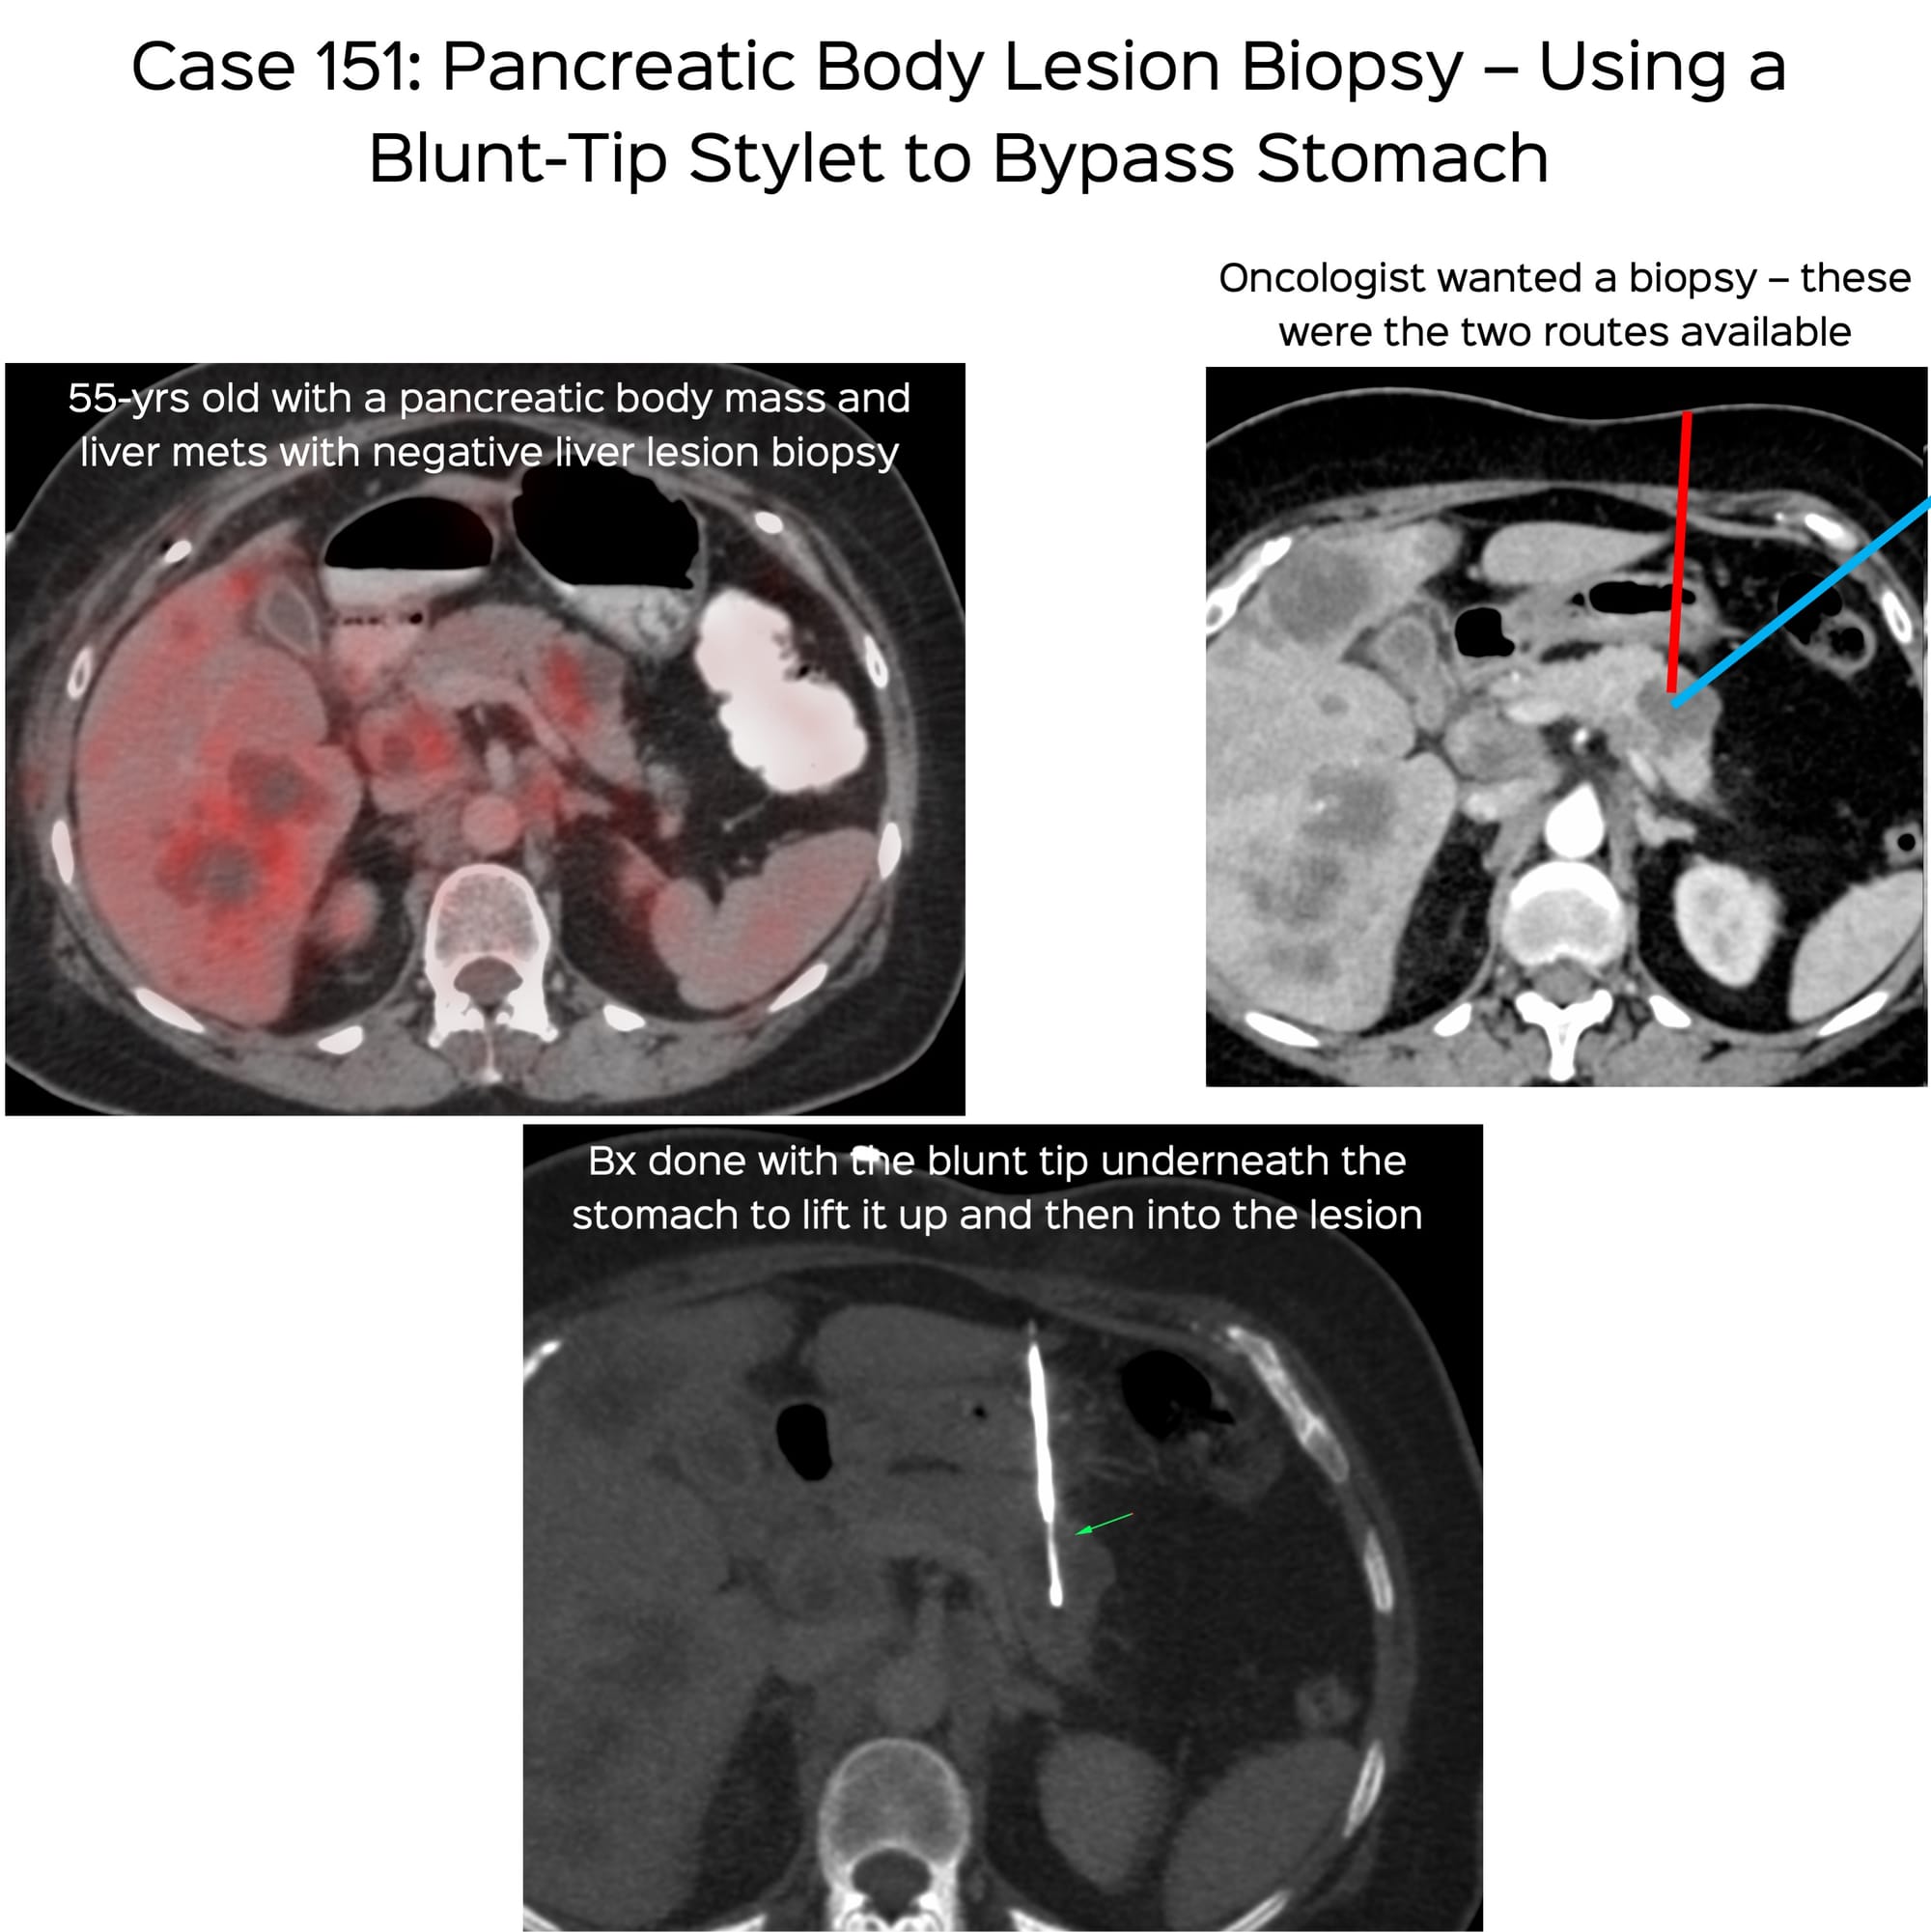

Case 151: Pancreatic Body Lesion Biopsy – Using a Blunt-Tip Stylet to Bypass Stomach